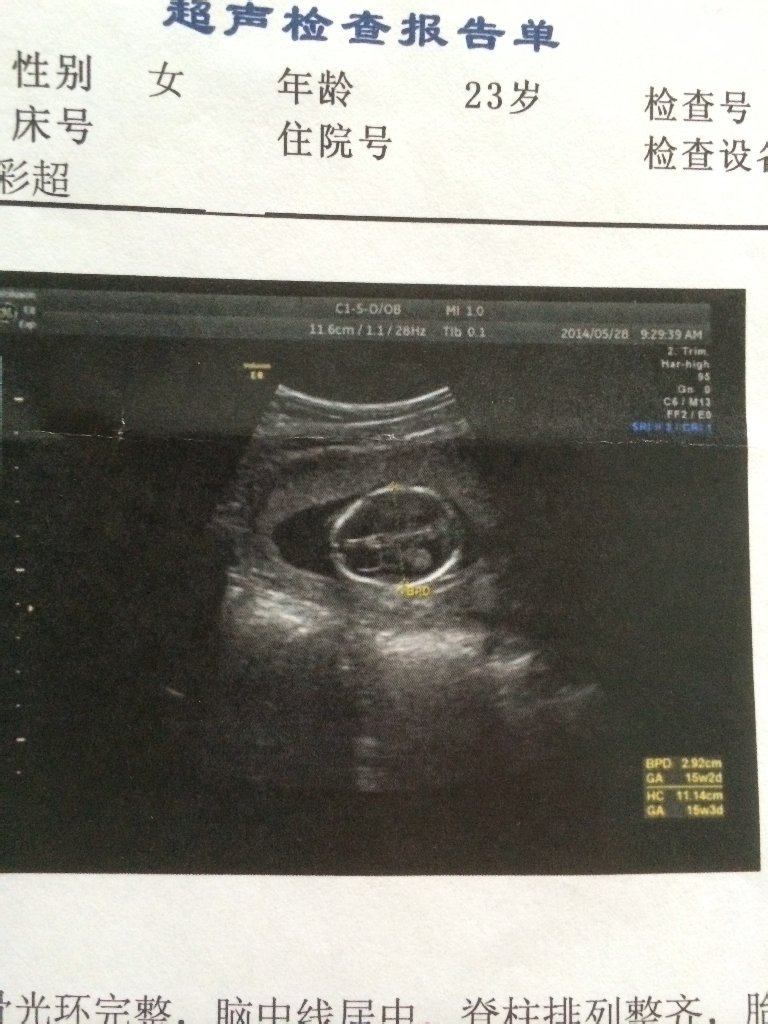

末次月经为阳历2月4号,应该为十六周了吧,今天彩超检查结果十五周,胎头双顶径2.9cm。HC11.14cm,BPD2.9cm,颅骨光环完整,脊柱整齐,胎心规律,回声均匀,羊水深径2.9cm。透声好。这个数据正常吗,是不是胎儿有点小。